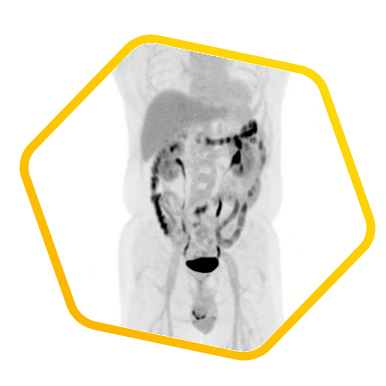

脑神经内分泌肿瘤

双示踪剂PET/CT (F-18 FDG及Ga-68 DOTATATE) 用於评估脑神经内分泌肿瘤体内的扩散情况